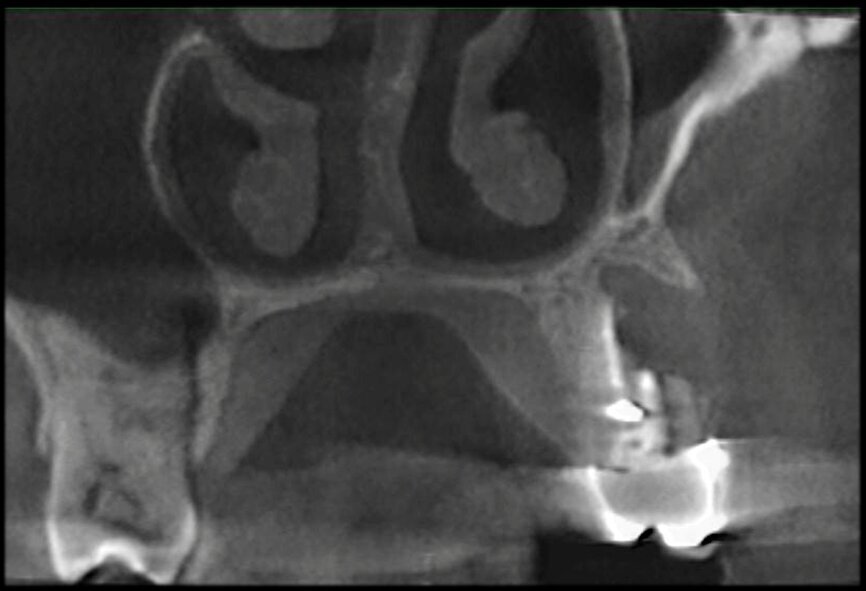

The case with which I would like to start my clinical review is a perfect example of how difficult it is to establish the origin of the patient’s symptoms on the basis of an intraoral radiograph alone. Not only does the 2D study fail to establish with certainty the presence of a lesion, but more importantly, it is impossible to establish the size, morphology and type of the lesion. An analysis of the 3D imaging, however, provides a clear picture of the clinical situation: the coronal and sagittal slices revealed the presence of a large lesion extending from the apex of the mesial root of this molar to the furcation, while the axial slices allow us to conduct a precise analysis of the endodontic anatomy and, in particular, the shape of the mesial root, which in this case was fused with the palatine root. A full overview of the case can, therefore, guide the decision-making process and direct the treatment plan towards a specific type of treatment (Figs. 1–4).